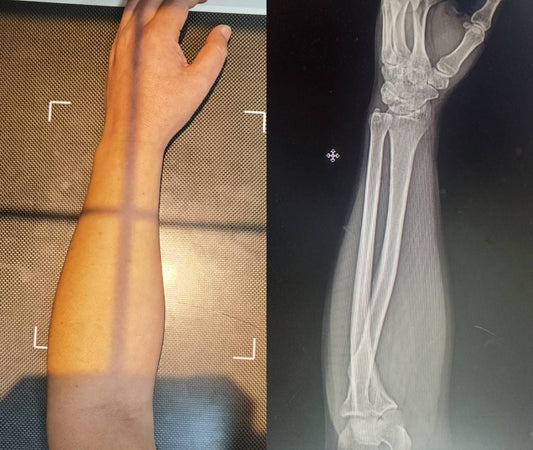

An actual medical X-ray of a human forearm in the same vertical mouse position, revealing that the radius and ulna bones are still crossed, labeled 'Anatomical Reality.' This visual evidence refutes the claim that vertical mice uncross forearm bones.

The "Uncrossed Bones" Lie: X-Rays Reveal the Tr...

Marketing claims vertical mice "uncross" your bones to prevent pain. We bought some tape and fired up an X-ray machine to prove why that is anatomically impossible.